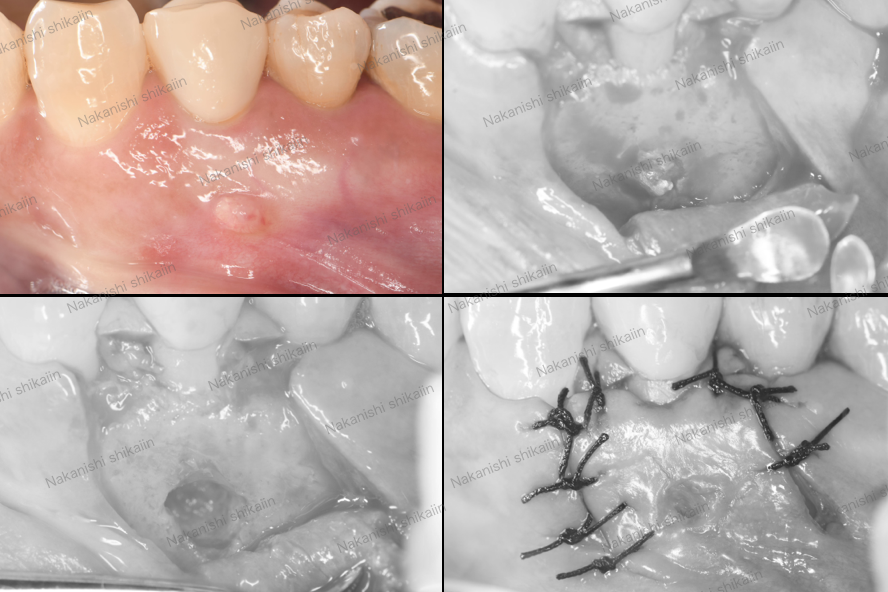

粘液貯留嚢胞の治療について、実際のところを説明していきます。写真のように、唇の内側が水脹れのように膨らんでいる箇所があります。これを切除してきます。

まずは該当部位の周りに局所麻酔を行います。その後、切開し、ピンセットで優しく開いていきます。

ぷくっとしているところがわかるでしょうか。これが唾液腺です。写真は、ある程度大きなものを取り除いた後のものです。

切除した唾液腺の写真です。このように、多数の小さな唾液腺を取り除きました。

大きなものから小さなものまであります。主原因は大きなものですが、小さなものを取り除いておかないと、後にこれが膨らんでいき、再発となります。見える範囲で全て取り除くことが大切です。

最後は切開した部分を縫合します。唇は内側は粘膜ですが、外側になれば上皮になるので、優しく縫い合わせていきます。きつく縫合すると、唇につっぱり感が出るので、緩く縫合することが大切です。

約1週間後に抜糸します。その後は何もなければ受診することなく終了です。